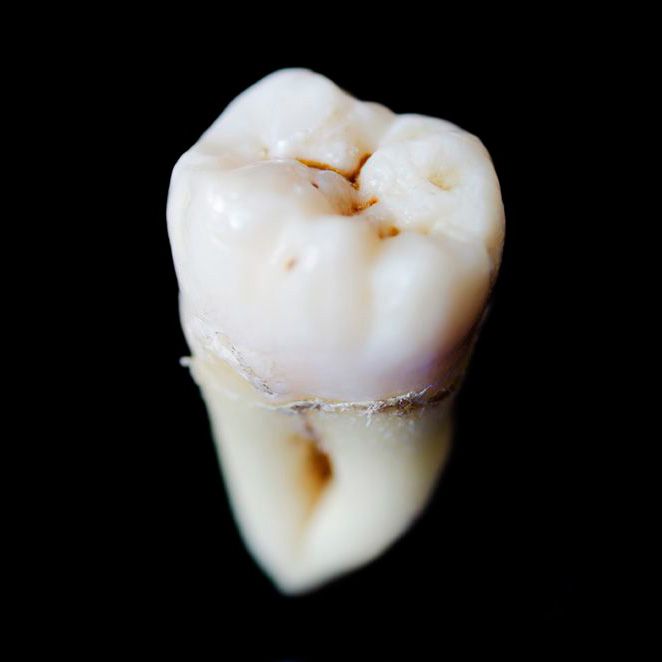

Dental Sealants

Along with routine cleanings, treatment with sealants are very effective at helping prevent tooth decay. A sealant is a liquid plastic coating that Dr. Slaman will apply to the tops of your molars. After it hardens, it will keep food particles from accumulating in the pits and grooves on your teeth. Dental sealants are appropriate for both children and adults who want to protect their smiles from future decay. The Center for Disease Control has found that sealants can reduce the risk of cavities by nearly 80 percent, especially in school-age children.